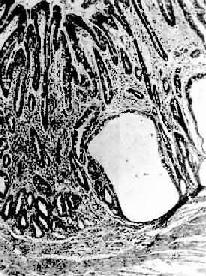

胃粘膜肠上皮化生

图10-4 胃粘膜肠上皮化生

胃粘膜上皮出现多量充满粘液的杯状细胞